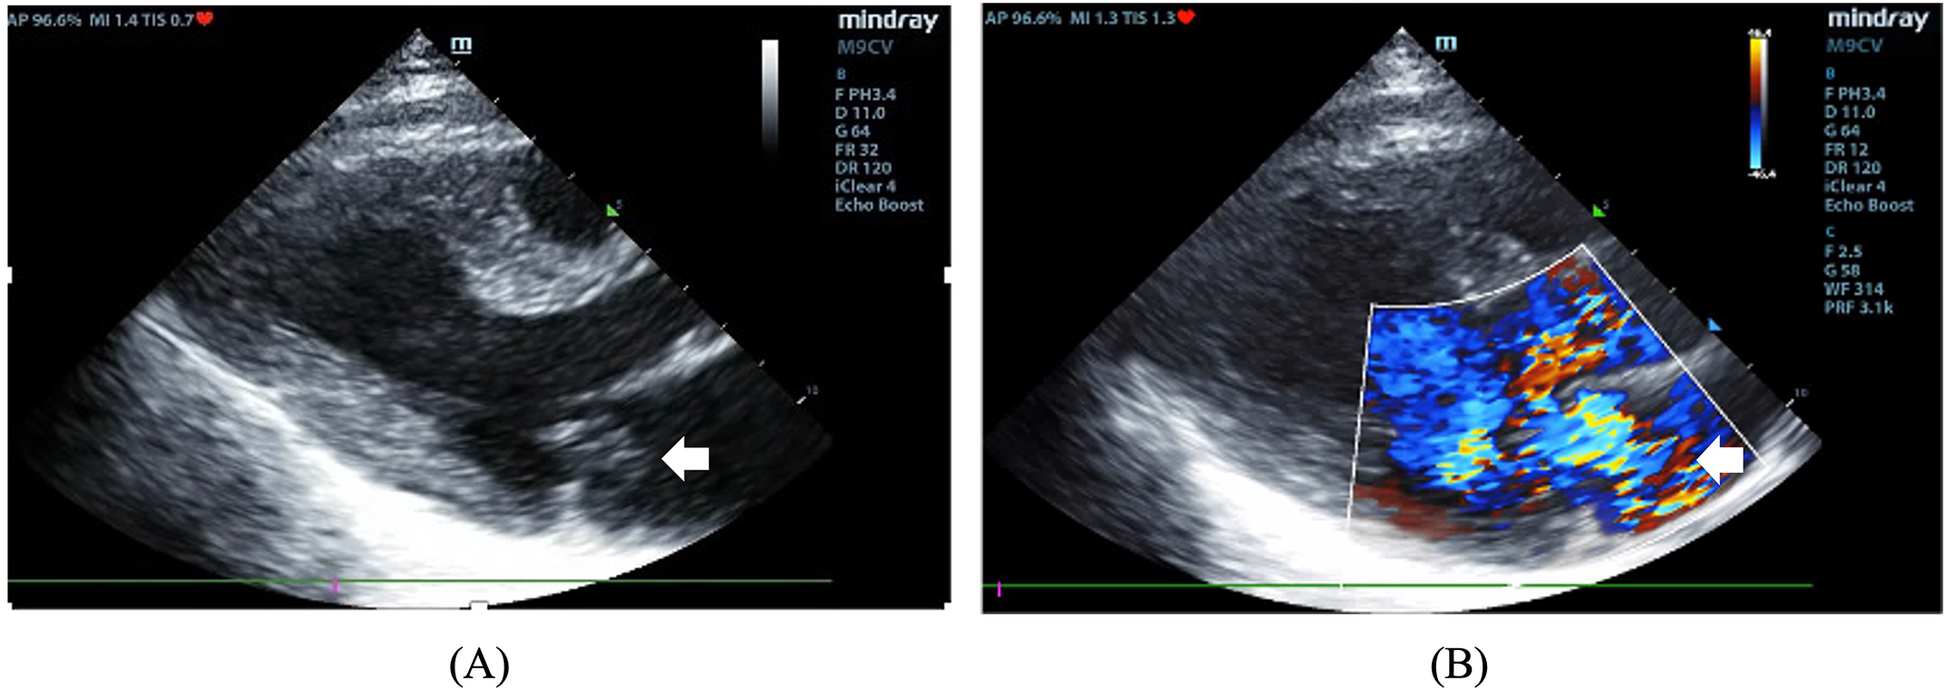

Figure 2

(A) The two-dimensional image showing a mass protruding into the left atrium (arrow). (B) Color Doppler image showing severe mitral regurgitation.

On admission, she exhibited signs of acute left heart failure. Physical examination documented a temperature of 36.3°C, tachycardia (145 bpm), hypotension (92/52 mmHg), tachypnea (28 breaths/min) with oxygen saturation 88% on room air. Widespread bilateral pulmonary crackles and an apical gallop rhythm with a grade III/VI holosystolic murmur at the mitral area were noted. Blood tests revealed elevated levels of C-reactive protein (37.5 mg/L, normal < 3 mg/L) and N-terminal B-type natriuretic peptide (12,855 pg/mL, normal < 125 pg/mL), while white blood cells (WBC) (8.12 × 109/L), platelet (257 × 109/L), hemoglobin level (143 g/L), erythrocyte sedimentation rate (16 mm/h), and hepatic and renal function were all normal. Chest computed tomography (CT) showed extensive bilateral pulmonary infiltrates with significant consolidation (Figures 1A–C). The electrocardiogram indicated supraventricular tachycardia at 164 bpm with 1 mm ST segment depression in leads V1 to V6. Transthoracic echocardiography revealed mitral valve papillary muscle rupture and a suspicious mass-like lesion protruding into the left atrium (Figures 2A,B). Emergent coronary computed tomography angiography demonstrated chronic occlusion of the left anterior descending artery, with retrograde perfusion supplied by collateral vessels originating from the circumflex artery, effectively excluding acute coronary syndrome.